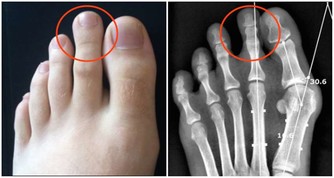

腿腳是骨骼、肌肉、關節形成的“鐵三角”,幾乎承載著身體的整個重量,僅膝蓋就承受9倍於體重的壓力。

負擔過重、行動姿勢不當、寒氣侵入等都會讓腿腳受傷。另外,腿腳最容易受到傷害的地方是關節。